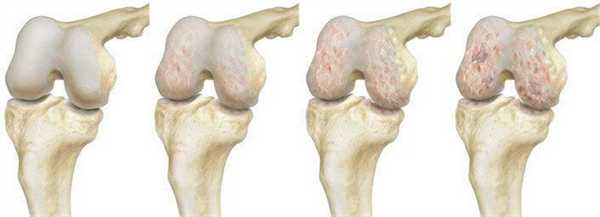

Динамика разрушения хрящевой поверхности.

Деформирующий остеоартроз — одно из ведущих заболеваний опорно-двигательного аппарата. Он проявляется дегенеративно-дистрофическими изменениями суставных поверхностей. Частота встречаемости составляет от 3 до 12% среди взрослого населения. В этом показателе на первом месте стоит поражение тазобедренного сустава, а на втором - коленного.